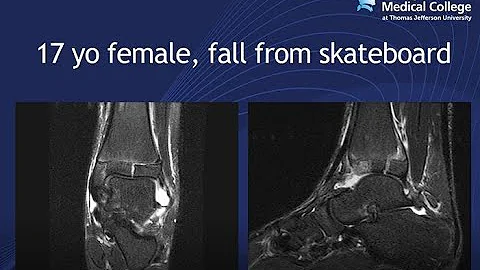

Emory MSK E-Lecture Series - Dr. Paul Read.

Imaging Young Athletes - They Are Not Little Adults!! Dr. Read of Jeff...